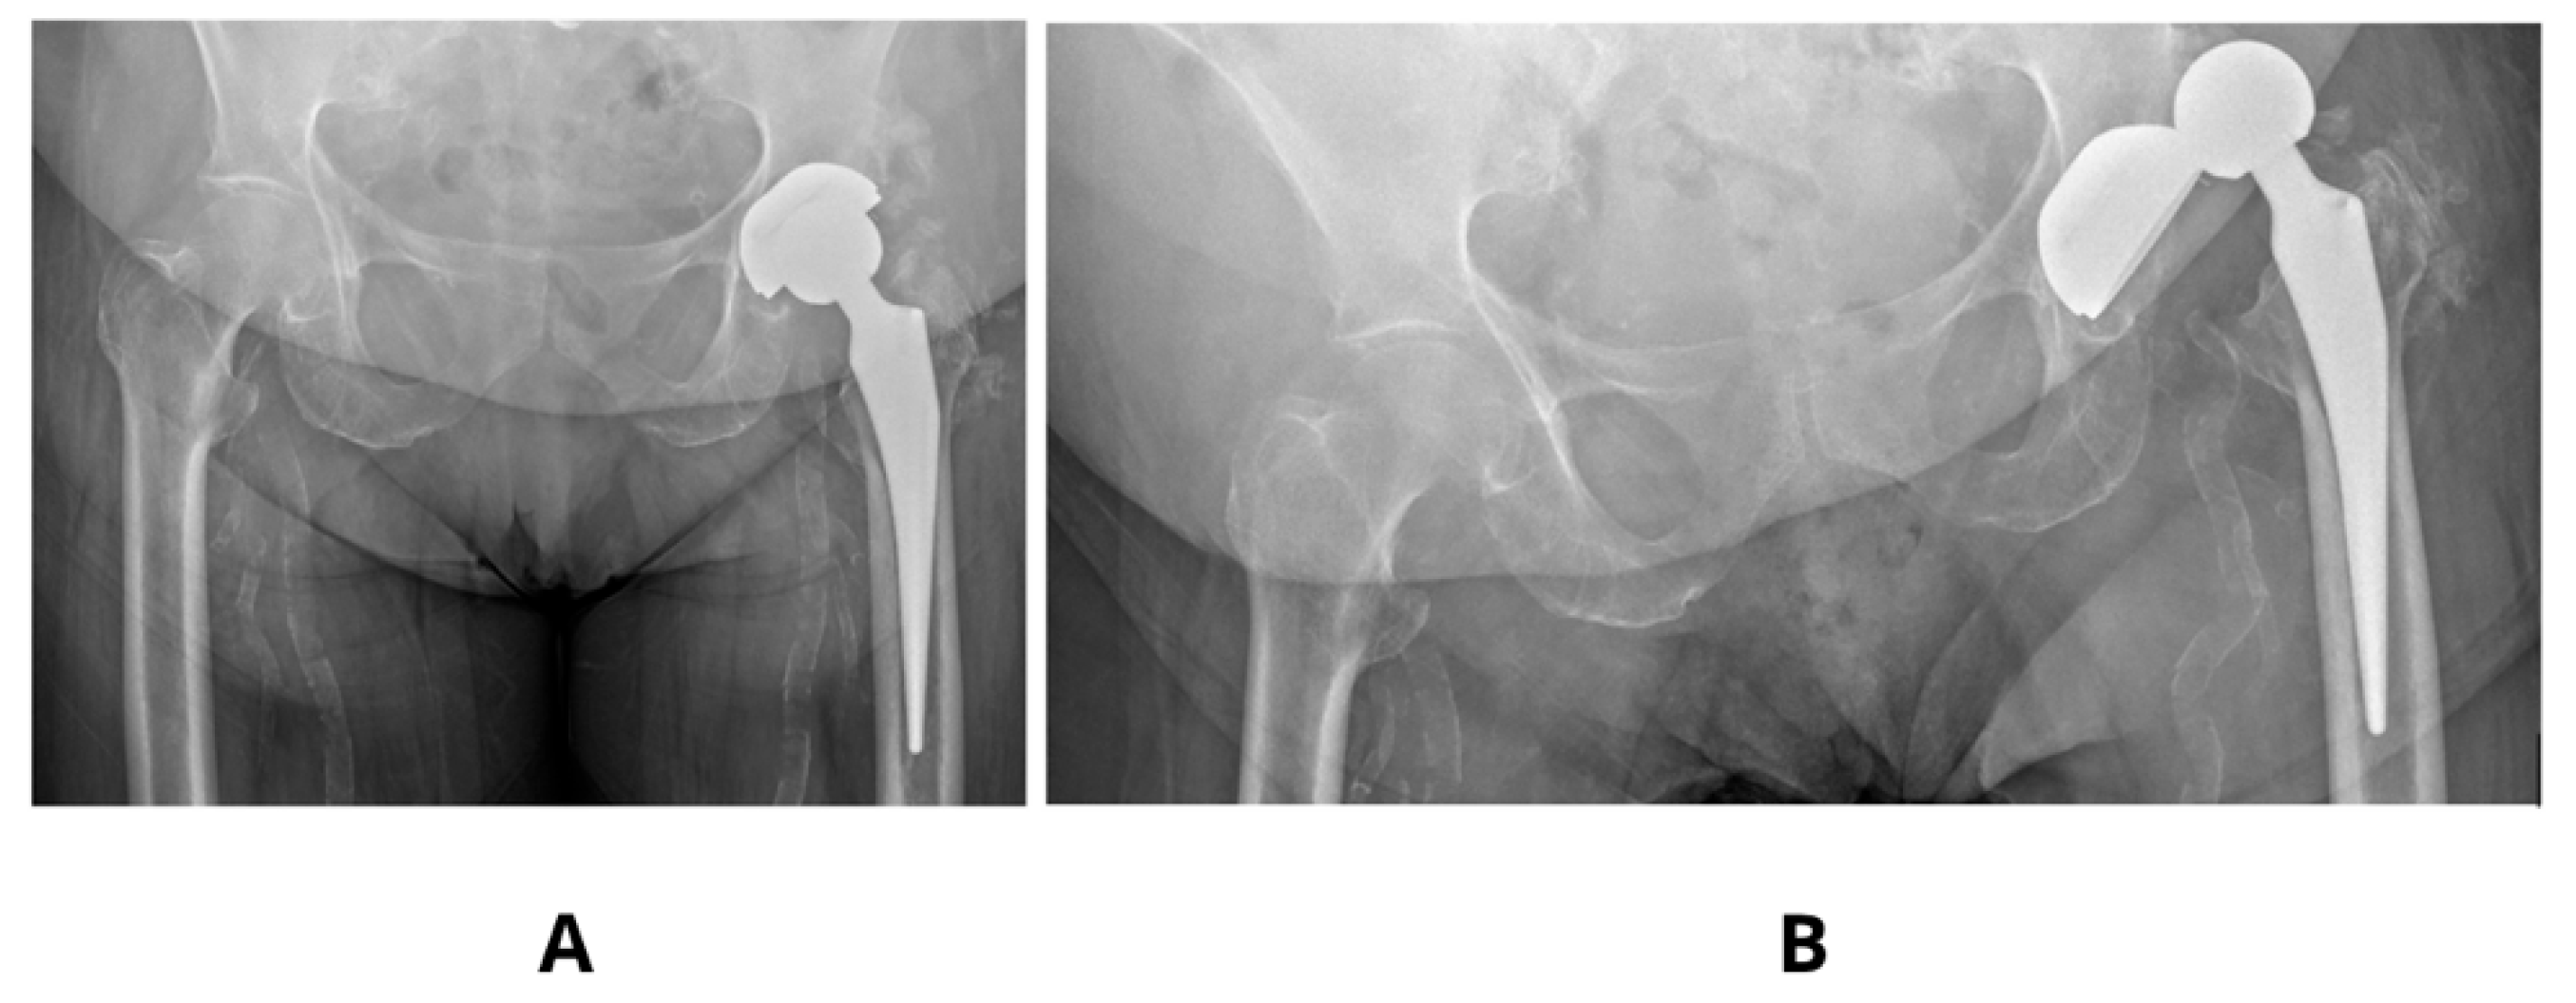

Literature examples emphasizes that precise acetabular positioning within the so-called functional safe zone is essential for minimizing biomechanical complications. According to Teja et al. [17] even minor deviations outside the 30–50° inclination and 5–25° anteversion range can impair prosthesis biomechanics and compromise functional stability. Observed in our studies decrease in SF to values as low as 2–3 in models with increased anteversion (30°) and shallow stem insertion highlights the sensitivity of these parameters and aligns with clinical findings, finding its confirmation in our clinical observations [Figure 4].

Figure 4. Clinical case showing an acetabulum with increased anteversion and inclination angle 60°—(A,B). Dislocation of the same prosthesis—(C).